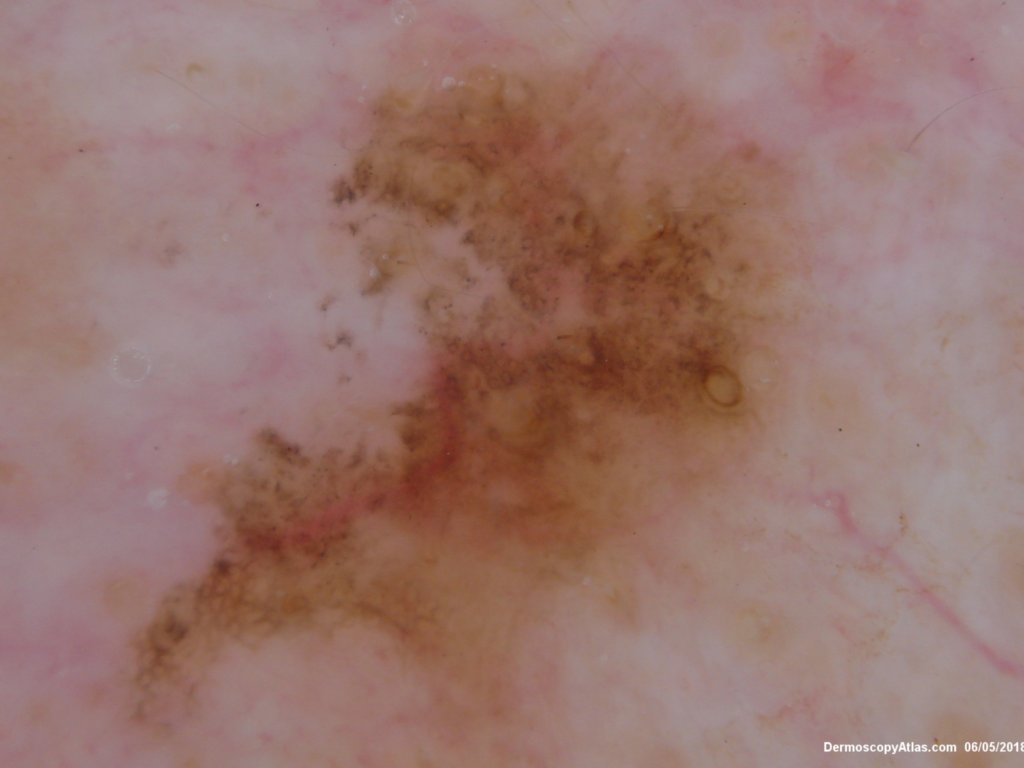

Site: Neck side

Diagnosis: Pigmented Intraepidermal carcinoma

Type: Dermlite Polarised

Submitted By: Ian McColl

Some pigmented lesions look melanocytic, However this is a pigmented intraepidermal carcinoma. Some areas show more full thickness atypia than others. The dermatoscopy shows some dots in rows but there are other grey dots showing regression at one edge.